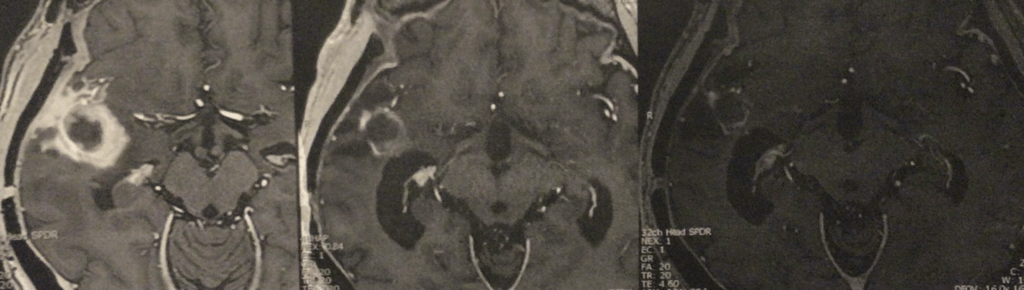

以下是不同时间点的影像对比:

2024/09 2024/12 2025/03